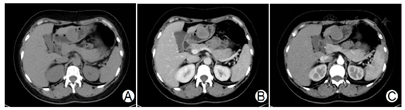

CT检查提示胃窦大弯侧外缘可见椭圆形软组织肿块影,边界清晰,大小约3.5×3.0cm,增强扫描呈渐进性强化,临近胃壁未见明显增厚,腹腔及腹膜后未见明确肿大淋巴结(图1)。